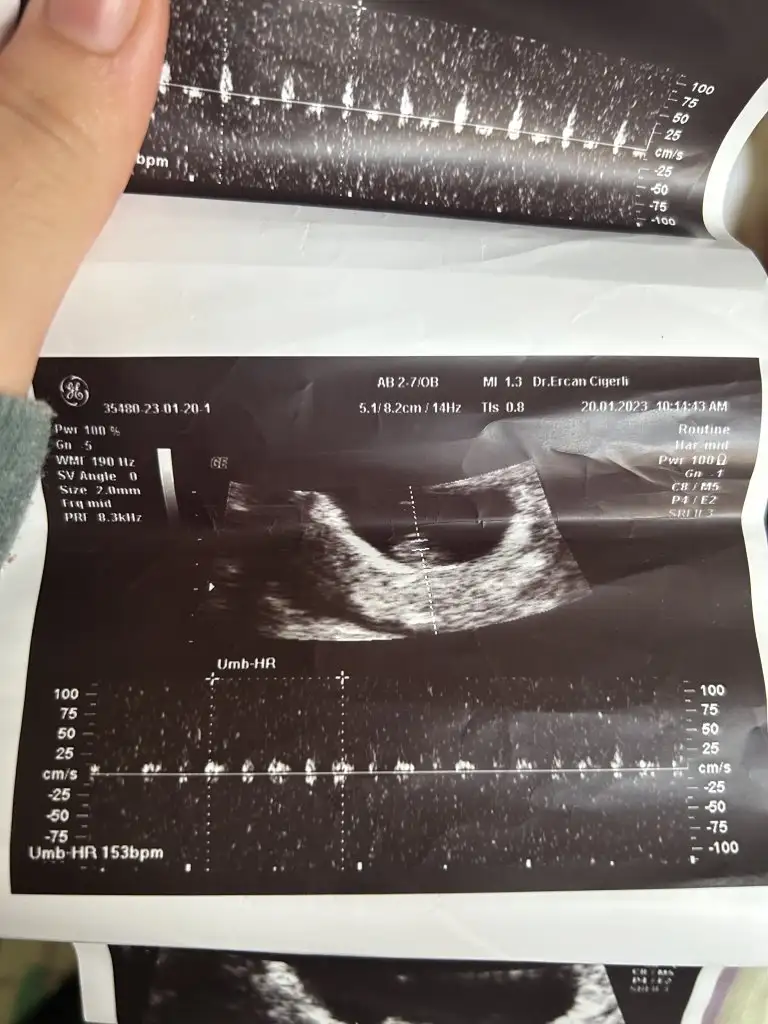

Pekiii bende ne dersin ?

Üstteki 9 haftalik diger ikisi 7 haftalik, ve vaginal ultrason :)